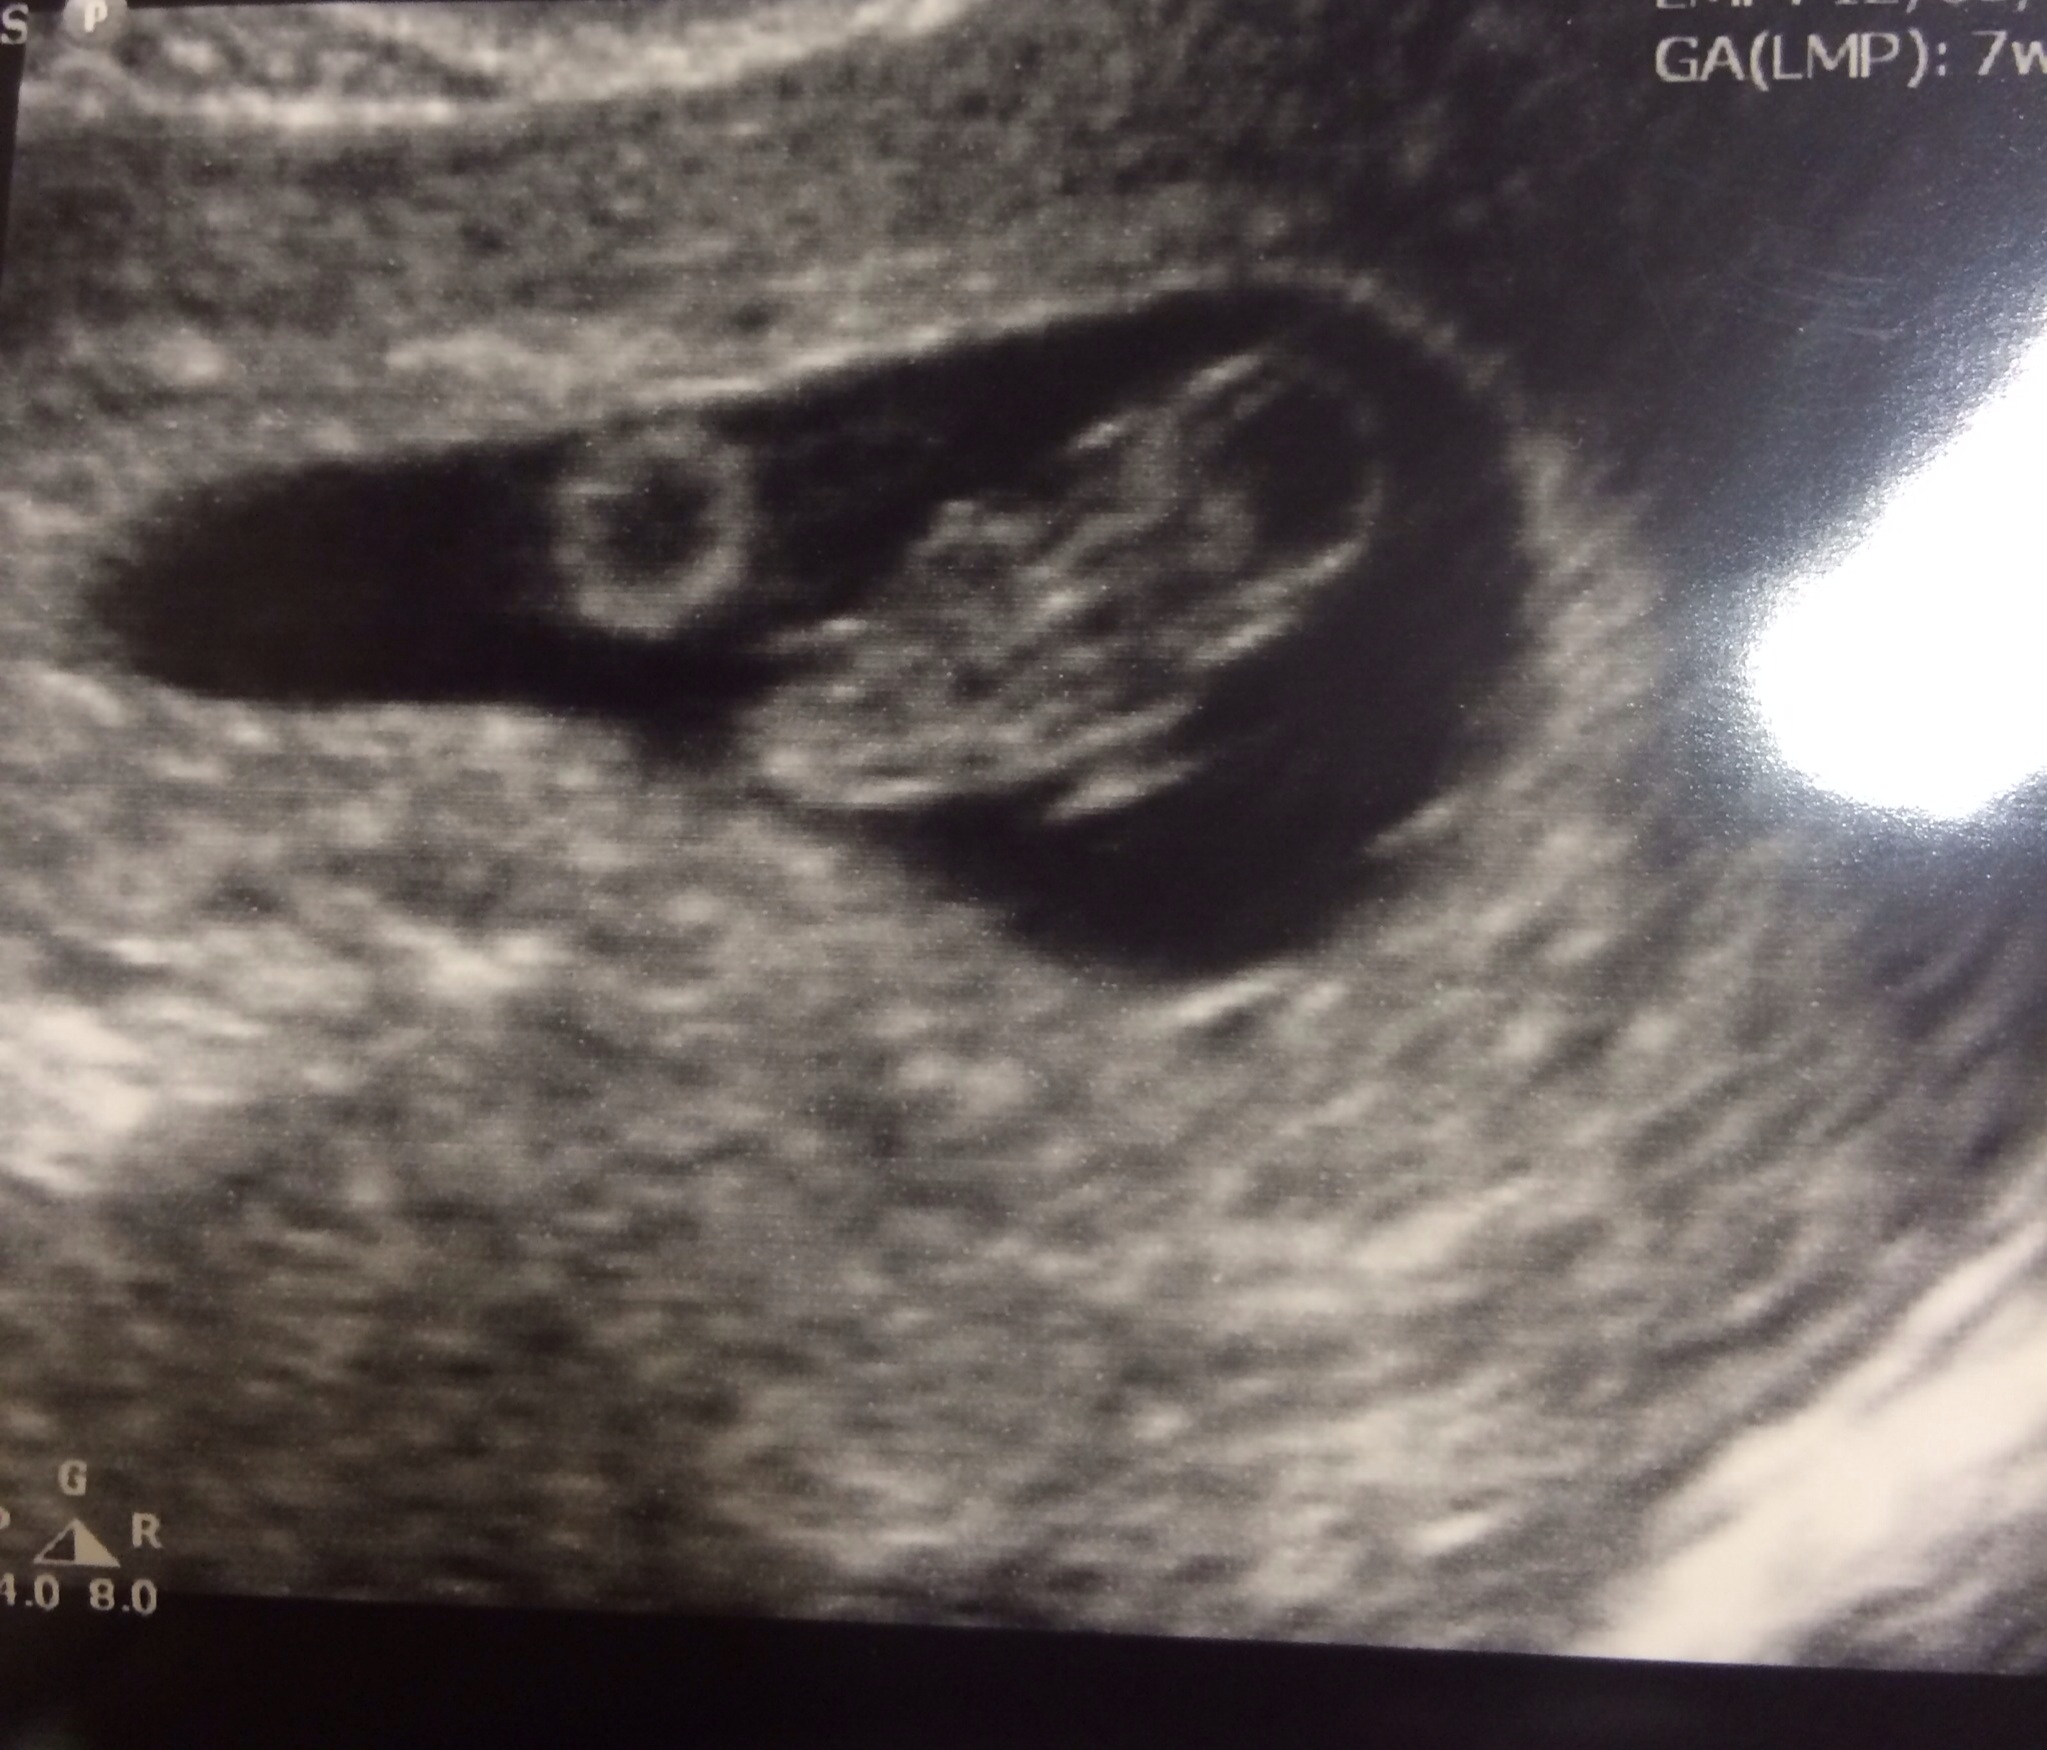

First Ultrasound!!! Went perfect!

I had my first ultrasound today and it went absolutely perfect. Doctor said everything looks great. The heartbeat was 140bmp and I was measuring 7w4d. I just can't believe I'm growing a person! So awesome!!!!